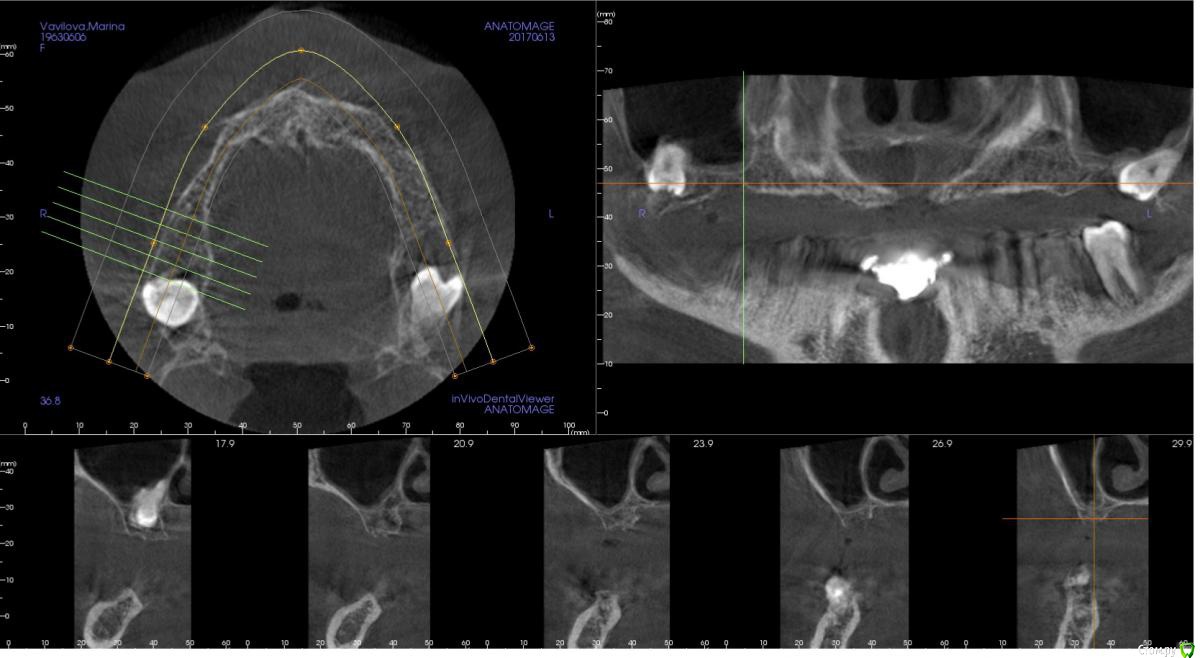

kamranchick Опубликовано 2 ноября, 2017 Поделиться Опубликовано 2 ноября, 2017 (изменено) Планируется установка 3 имплантатов в 1 сегменте, и будет балочная конструкция.хочется пойти двухэтапным протоколом. так как гигиена и вредные привычки меня отпугивают.Какой вариант тут будет предпочтительным Изменено 2 ноября, 2017 пользователем kamranchick Ссылка на комментарий

kamranchick Опубликовано 2 ноября, 2017 Автор Поделиться Опубликовано 2 ноября, 2017 А сколько всего планируется имплантов? А если только во фронте 4 поставить?6 имплантатов, 3 с одной поставил, теперь 3 с другой, во фронте кости кот наплакал( Ссылка на комментарий

Тимур86 Опубликовано 2 ноября, 2017 Поделиться Опубликовано 2 ноября, 2017 яб синус лучше сделал Ссылка на комментарий

zzkz Опубликовано 3 ноября, 2017 Поделиться Опубликовано 3 ноября, 2017 согласен за синус и отсроченную нагрузку через 6 мес Ссылка на комментарий